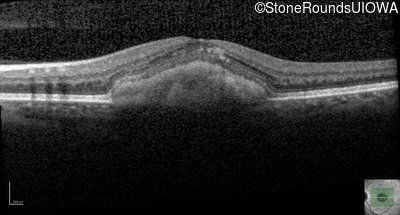

Age at visit: 29 years

This 29 year old woman recently had macular abnormalities noticed on routine eye exam. She has noticed some reduction of her central vision after exposure to bright light which slowly recovers over a period of minutes.